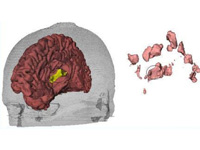

Generation of Connectivity-Preserving Surface Models of Multiple Sclerosis Lesions

In this article we introduce a software tool to build 3D surface models of Multiple Sclerosis (MS) brain lesions from 2D image stacks typically obtained through Magnetic Resonance Imaging (MRI). This tool allows users to create 3D models of MS lesions quickly and visualize the lesions and brain tissue using various visual attributes and configurations.

A Novel MRI Visualization Tool for White Matter Pathology in Multiple Sclerosis

We developed a tool to visualize MS lesions and their 3D surface models to show changes in the lesions over time. These can be shown as an animation to elucidate differences across scanning sessions. With this software, a volumetric sub-region can be selected from the 3D model for zooming or animation, and a point on the 3D model can be selected to highlight all lesions connected to it. The total volume of lesions can be calculated, displayed as a chart, and exported.

Concurrent Visualization of and Mapping between 2D and 3D Medical Images for Disease Pattern Analysis

We present a software tool to highlight and display regions of interest in 2D medical images and their 3D mesh model counterparts. This tool can help researchers visualize and compare brain lesions and tissues in 2D and 3D at the same time.